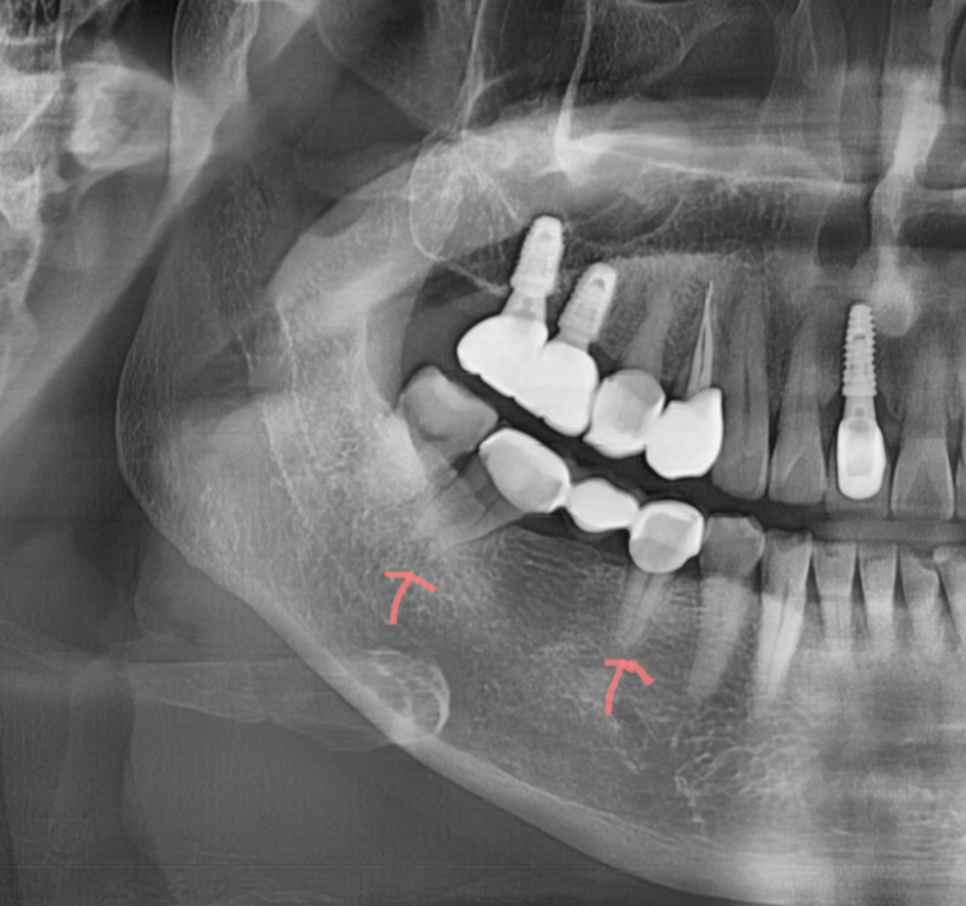

240208 오래된 브릿지 제거 후 양쪽 건강했던 치아가 망가져 있습니다.

단점으로는 건강한 인접 치아를 삭제해야합니다.

이는 장기적으로 보았을 때 양 옆 치아의 수명까지 줄일 수 있습니다.

브릿지를 하지 않았더라면

치아를 삭제할 일도 없었으니까요.